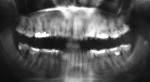

Five cases met the criteria as set forth in the study and are summarized in Table 1; radiographs of the five cases are shown in Figure 1 through Figure 21. Ages ranged from 15 to 48 years. Four patients were male and one female. All five cases involved Caucasian patients. Two cases involved the distal roots of mandibular first molars bilaterally (Figure 1, Figure 2, Figure 3, Figure 4, Figure 5, Figure 6, Figure 7, Figure 8, and Figure 18, Figure 19, Figure 20, and Figure 21); one case involved both roots of the mandibular first molars bilaterally (Figure 11, Figure 12, Figure 13, Figure 14); and two cases involved the mandibular second premolar unilaterally (Figure 9 and Figure 10, and Figure 15, Figure 16, and Figure 17). Two of the patients presented with symptoms similar to cracked-tooth syndrome (Table 1, Case 3 and Case 4), one with “chronic reversible pulpitis” (Table 1, Case 1), and two were asymptomatic (Table 1, Case 2 and Case 5).

Patients in all five cases exhibited PARR of the involved roots, as previously described (Figure 1 through Figure 21).40 The roots showed shortening and blunting of the apex of greater than 2 mm in all five cases. In three of the five cases, the PARR self-arrested without any treatment. The mandibular left first molar in Case 1 (Figure 5, Figure 6, Figure 7, and Figure 8) received conventional root canal therapy (RCT), while the mandibular right first molar in Case 3 (Figure 11, Figure 12, Figure 13, Figure 14) received a bonded ceramic crown. The PARR appears to have arrested in these two cases, and the outcome of the treatment in relation to the resorption could not be determined. The symptoms the patients were experiencing did eventually resolve. Consequently, all five study cases became symptom-free, including the patient who received conventional RCT (Case 1).

The Case 1 patient, who was the son of the Case 2 patient, was observed in preoperative orthodontic records prior to initiating orthodontic therapy (Figure 1 and Figure 2). The Case 1 patient also demonstrated PARR of the mandibular anterior incisors post-orthodontic therapy (Figure 8). The Case 5 patient had serial extractions completed as a child, but no fixed or removable orthodontic appliances were utilized. Past medical histories were all noncontributory (Table 1). No cases of MICR or MIAR were identified in any of the files reviewed.

LIAR is similar both radiographically and in clinical location to MIAR. Both conditions exhibit PARR without ankylosis involving the mandibular molars and premolars. However, MIAR involves additional teeth and is progressive, with resultant loss of teeth, whereas LIAR involves one to three teeth and is self-limiting. Clinical history and a full-mouth radiographic series or panoramic radiograph would aid in differentiating these two conditions. Utilization of cone beam computed tomography (CBCT) imaging may be of benefit when available, but its utilization in LIAR cases would require further study.

Metabolic and systemic disturbances—such as hormonal imbalances,12 Paget’s disease of bone,55,56 hyperparathyroidism,25 Gaucher’s disease,40 hypophosphatasia,57 Papillon-Lefevre syndrome,58 hemifacial atrophy,59 renal and liver diseases,26,60 focal dermal hypoplasia (Goltz syndrome),61 familial expansile osteolysis,62 and osteogenesis imperfecta63—may need to be considered. However, these disease processes produce a radiographic pattern similar to MIAR and MICR but should be considered in LIAR. A full-mouth radiographic series or panoramic film would be indicated in suspected cases. CBCT images may be beneficial if available.